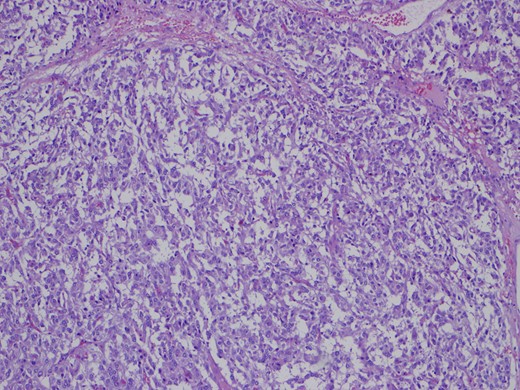

One month later the patient was reoperated via an open approach, which revealed a tumoral lesion in the inter-aorto-cava location, from the right diaphragmatic pillar to the right renal artery. No intraoperative complications were reported and the post-operative period was uneventful. Histological result revealed an 84 g capsulated, solid tumor, with 80 × 60 × 25 mm3. Immunohistochemistry revealed positivity for chromogranin and synaptofisin, compatible with paraganglioma (Figs 4–6). No vascular, lymphatic or capsular invasion was ocumented.